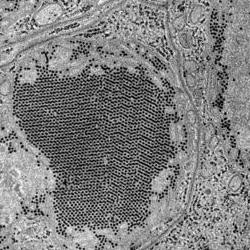

St. Louis Encephalitis (SLE) virus